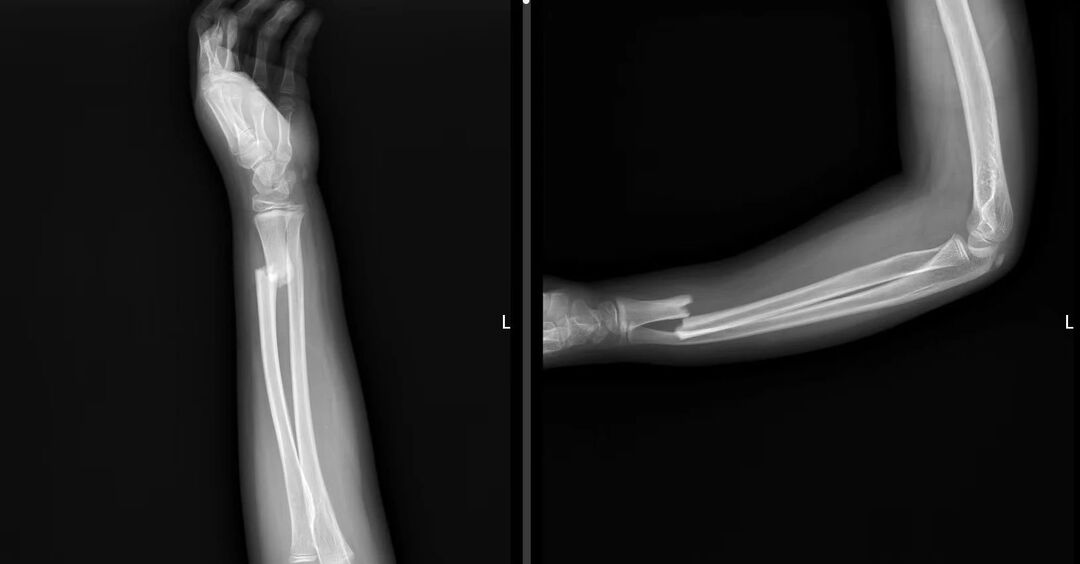

该名男孩,从小就酷爱运动,以足球为甚。尽管才11岁,在绿茵场上驰骋起来,颇有些球星的气度和风范。运动强健体魄的同时亦伴随风险。今年儿童节的第二天,男孩在踢球时跌倒致左桡尺骨下段青枝骨折,遂来到株洲市中医伤科医院小儿骨科门诊,接受中医正骨手法复位治疗。两个多月过去,孩子恢复得越来越好,对球场格外向往,早已蠢蠢欲动,于是在未完全恢复的状态下就上场踢球。结果,他再次跌倒,又是同一位置骨折,这次更严重,被诊断为左桡骨下段骨折全错位、左尺骨下段青枝骨折、下尺桡关节分离。眼看着骨折马上就好了,其父母懊悔不已,带着孩子住进伤科医院小儿骨科。

面对忧心忡忡的父母,该院小儿骨科主任彭真灵对男孩和家属一一安慰,待悬心落下,施以手法正骨复位,外敷中药,上小夹板外固定,外加中药活血化瘀、消肿止痛等对症处理。不过几日,肿痛消散明显,复查的X片显示,骨折的对位对线良好。